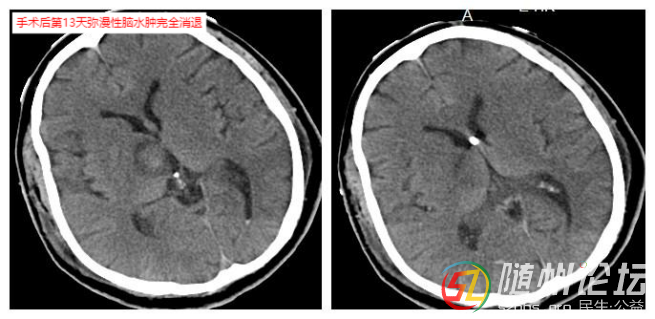

術(shù)后患者如預(yù)期出現(xiàn)彌漫性腦水腫,到術(shù)后第6天達到彌漫性腦水腫高峰,得益于冒著巨大風(fēng)險做的腦室外引流手術(shù),每日引流出血性腦脊液100多毫升,從根本上降低顱內(nèi)壓。醫(yī)療團隊日夜堅守,根據(jù)患者情況精細調(diào)整治療方案,在消腫和維持生命體征之間謹慎平衡。通過抗感染、氣管切開、早期促醒及中醫(yī)藥等綜合治療,患者終于在術(shù)后第13天度過最危險期,睜開眼睛,迎來生命曙光。